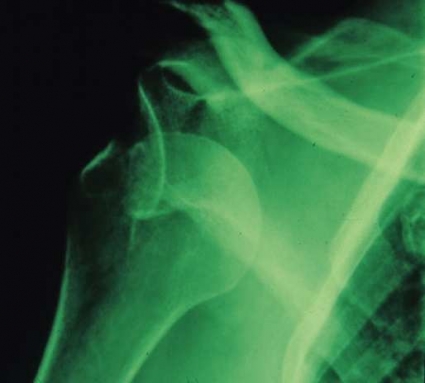

Rotatorkuffen är en senmanschett, huvudsakligen utgående från supraspinatus-, infraspinatus- och subskapularismuskulaturen. Denna senmanschett fäster på ledhuvudet. Med subakromiella smärttillstånd avses här en inklämning (impingement) av denna senmanschett och slemsäcken under acromion (Figur 2), ruptur i senmanschetten men också akromioklavikularledsartros.